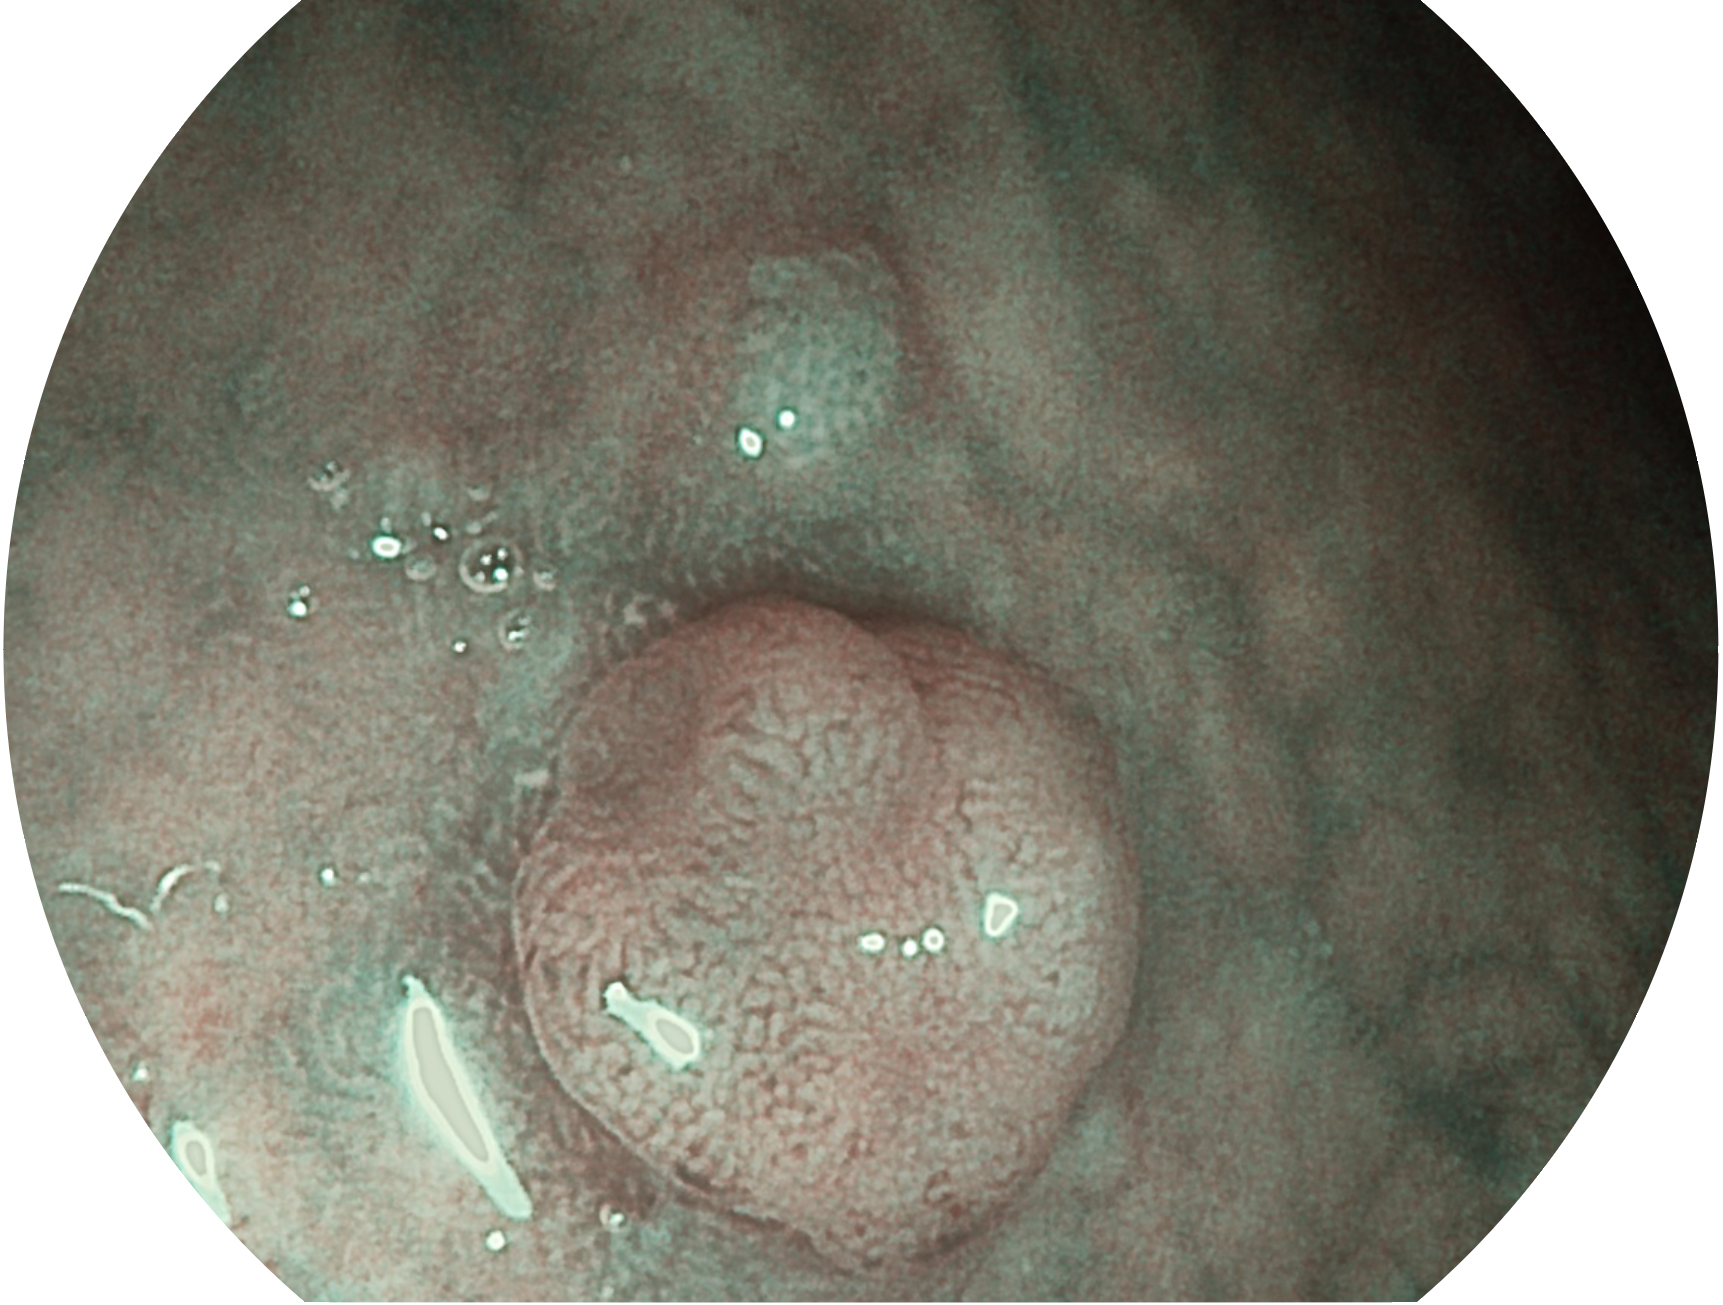

MILE米乐集团官网新开发的内镜染色技术,主要是基于多波长LED 光源的开发,VLS-55Q 四波长LED 光源是由四个不同颜色的LED光按照相应照明模式所规定的特定发光比例进行合束后形成,合束后形成的照明光的光谱由红光、绿光、蓝光及蓝紫光这四个不同的波段范围构成。具有更高光谱自由度,通过光谱比例的控制,实现了聚谱成像技术,英文全称为“Spectral Focused Imaging, SFI”,缩写为“SFI”和光电复合染色成像技术,英文全称为“Versatile Intelligent Staining Technology, VIST”,缩写为“VIST”。